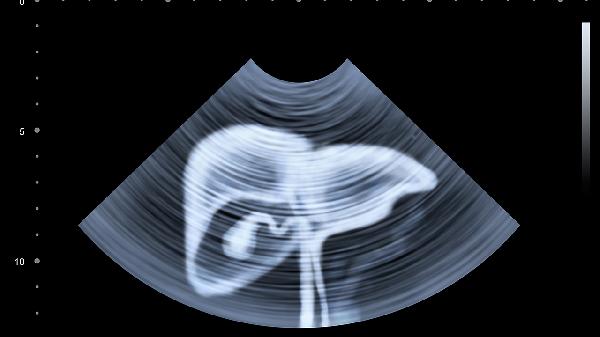

上腹部核磁共振检查主要针对肝胆胰脾等器官,下腹部核磁共振检查则侧重泌尿生殖系统和肠道病变。两类检查的适应症主要有器官结构异常、肿瘤筛查、炎症评估、血管病变及先天畸形五类。

上腹部核磁可清晰显示肝脏囊肿、胆管扩张、胰腺形态变异等结构改变,下腹部核磁则能发现肾脏发育不良、子宫畸形或前列腺增生等解剖学异常。检查无需造影剂即可获得三维立体图像,对软组织分辨率显著优于CT。